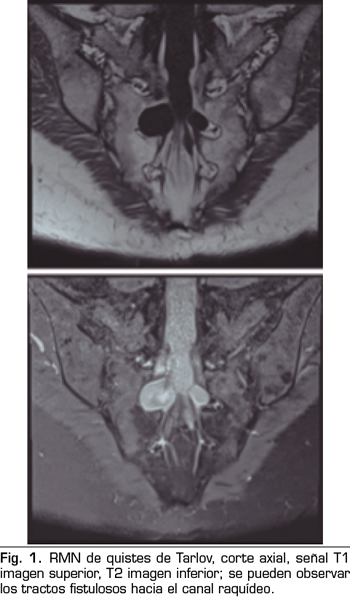

Los “quistes perineurales” o “Quistes de Tarlov” son alteraciones en la duramadre de las raíces nerviosas, que se producen más frecuentemente en la zona sacra. El diagnóstico suele ser casual mediante RMN; la incidencia es variable, debido a que el hallazgo es incidental. Habitualmente son asintomáticos, pero pueden producir radiculopatía, dolor perineal o vejiga neurógena, entre otros.

Figura 1